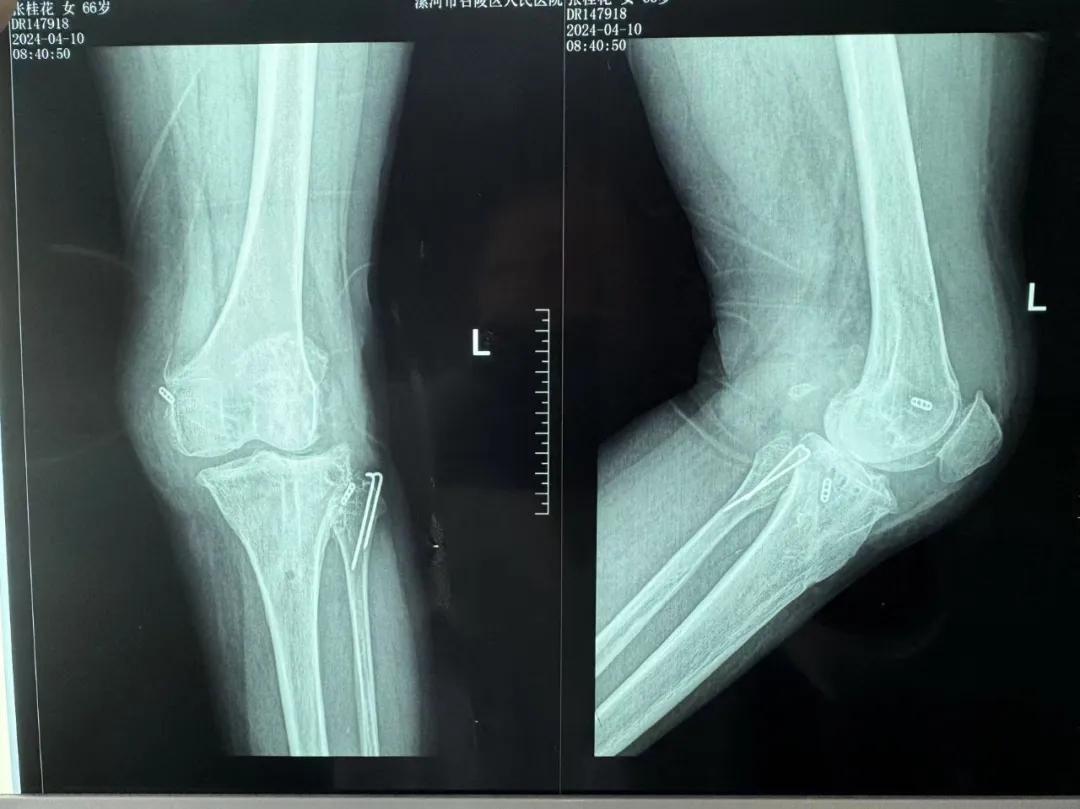

患者來(lái)院后,漯河市骨科醫(yī)院(漯河醫(yī)專(zhuān)二附院、漯河市立醫(yī)院)主治醫(yī)師康樂(lè)便成了她的管床醫(yī)生。在經(jīng)過(guò)詳細(xì)的術(shù)前診斷與檢查后,關(guān)節(jié)外科主任李付彬組織科室團(tuán)隊(duì)針對(duì)患者的診斷情況進(jìn)行術(shù)前討論——患者為重度膝關(guān)節(jié)骨關(guān)節(jié)炎,需進(jìn)行人工關(guān)節(jié)置換。但術(shù)前的評(píng)估結(jié)果顯示:患者膝關(guān)節(jié)側(cè)方不穩(wěn)定,單純行初次表面膝關(guān)節(jié)置換,術(shù)后仍會(huì)存在側(cè)方不穩(wěn)的情況,會(huì)影響術(shù)后效果以及假體使用年限,不僅無(wú)法完全恢復(fù)膝關(guān)節(jié)功能,還會(huì)加重患者的經(jīng)濟(jì)負(fù)擔(dān)。

為了盡可能給患者帶來(lái)更好的治療效果,減輕其經(jīng)濟(jì)負(fù)擔(dān),經(jīng)綜合評(píng)估后,李付彬主任帶領(lǐng)團(tuán)隊(duì)制定了最終的手術(shù)方案——決定使用髁限制性膝關(guān)節(jié)假體(LCCK)置換膝關(guān)節(jié)。作為解決患者病痛的最優(yōu)方案,這項(xiàng)手術(shù)具體實(shí)施的難度并不小,需要在術(shù)中根據(jù)截骨情況進(jìn)行多次評(píng)估和實(shí)時(shí)調(diào)整,這就要求主刀醫(yī)生不僅要具備過(guò)硬的專(zhuān)業(yè)技術(shù)與能力,還要能夠結(jié)合自身的經(jīng)驗(yàn)準(zhǔn)確判斷、精準(zhǔn)操作。

手術(shù)過(guò)程中,關(guān)節(jié)外科團(tuán)隊(duì)為患者進(jìn)行了標(biāo)準(zhǔn)截骨,經(jīng)過(guò)評(píng)估,患者膝關(guān)節(jié)仍存在膝關(guān)節(jié)側(cè)方不穩(wěn)定,便按照原定手術(shù)計(jì)劃使用LCCK假體進(jìn)行了膝關(guān)節(jié)置換。經(jīng)過(guò)再次評(píng)估,患者膝關(guān)節(jié)穩(wěn)定性恢復(fù),下肢力線正常,這臺(tái)高難度的LCCK膝關(guān)節(jié)置換手術(shù)在一小時(shí)內(nèi)便順利完成!術(shù)后第二天,患者就能夠自主下床負(fù)重活動(dòng),功能恢復(fù)良好。